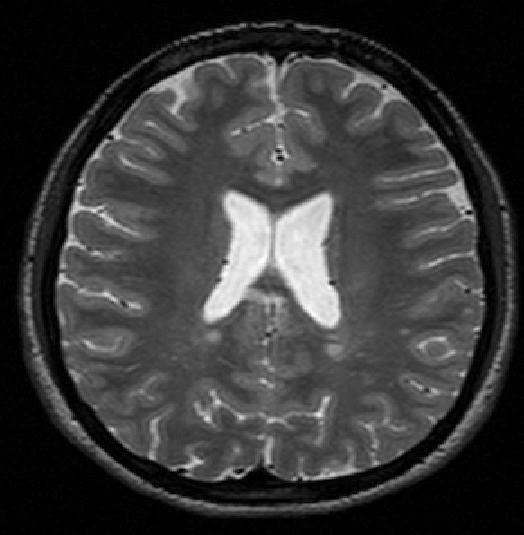

We use images from three different studies (see Fig. 1 for examples of slices):

10 MS patients from the MS Lesion Challenge [11] scanned at the Children’s Hospital of Boston (CHB), scanned with T1, T2 and FLAIR at 0.50.50.5mm resolution.

2.

- 3.

Here again the differences between study populations influence the class priors. On average, the percentage of voxels that are lesions are 1.6%, 2.6% and 0.2% in CHB, RSS and UNC respectively. The differences between subjects also vary: these are relatively small for CHB and UNC, but very large for RSS. In RSS, the subject with the least lesion voxels has only 0.08%, while the patient with the most lesion voxels has 14.3%.